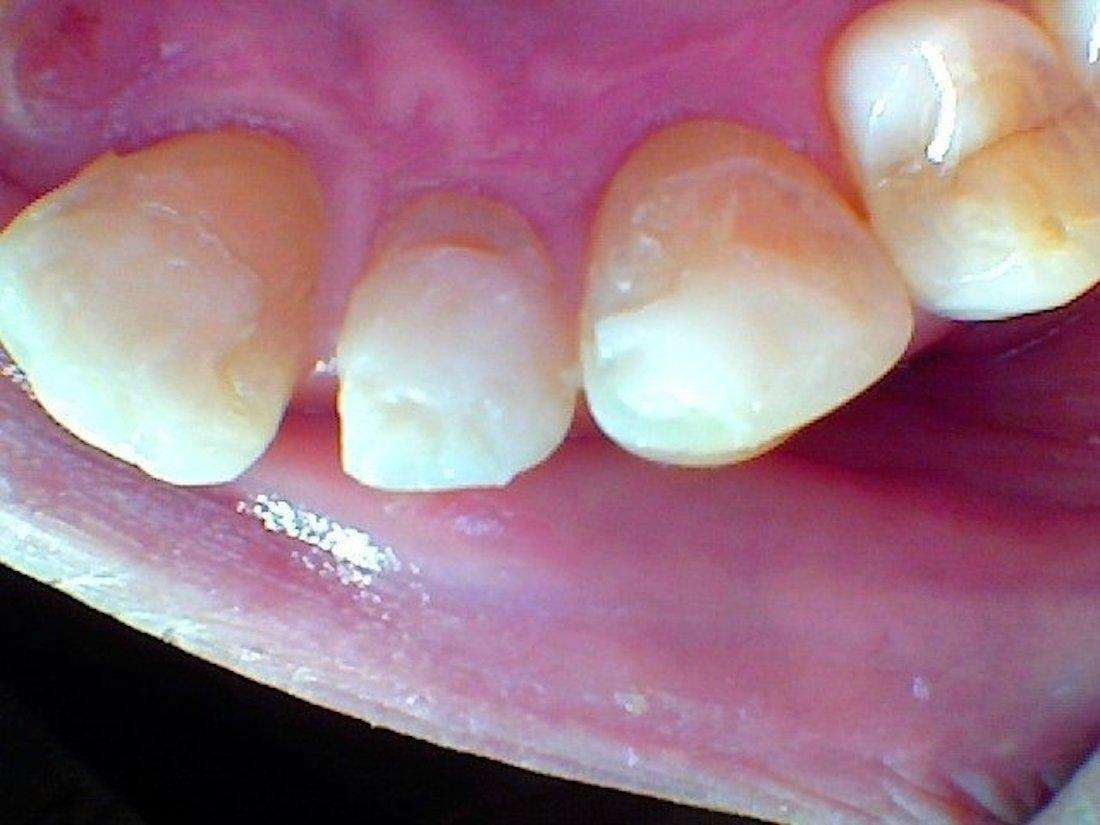

Cosmetic teeth bonding was performed here to restore teeth that were damaged from chronic grinding.

In the before photo, you can see the exposed inner layer of the tooth (dentin), which is yellow. These holes and chips can occur when grinding your teeth or frequently chewing on hard substances such as ice or any hard food.